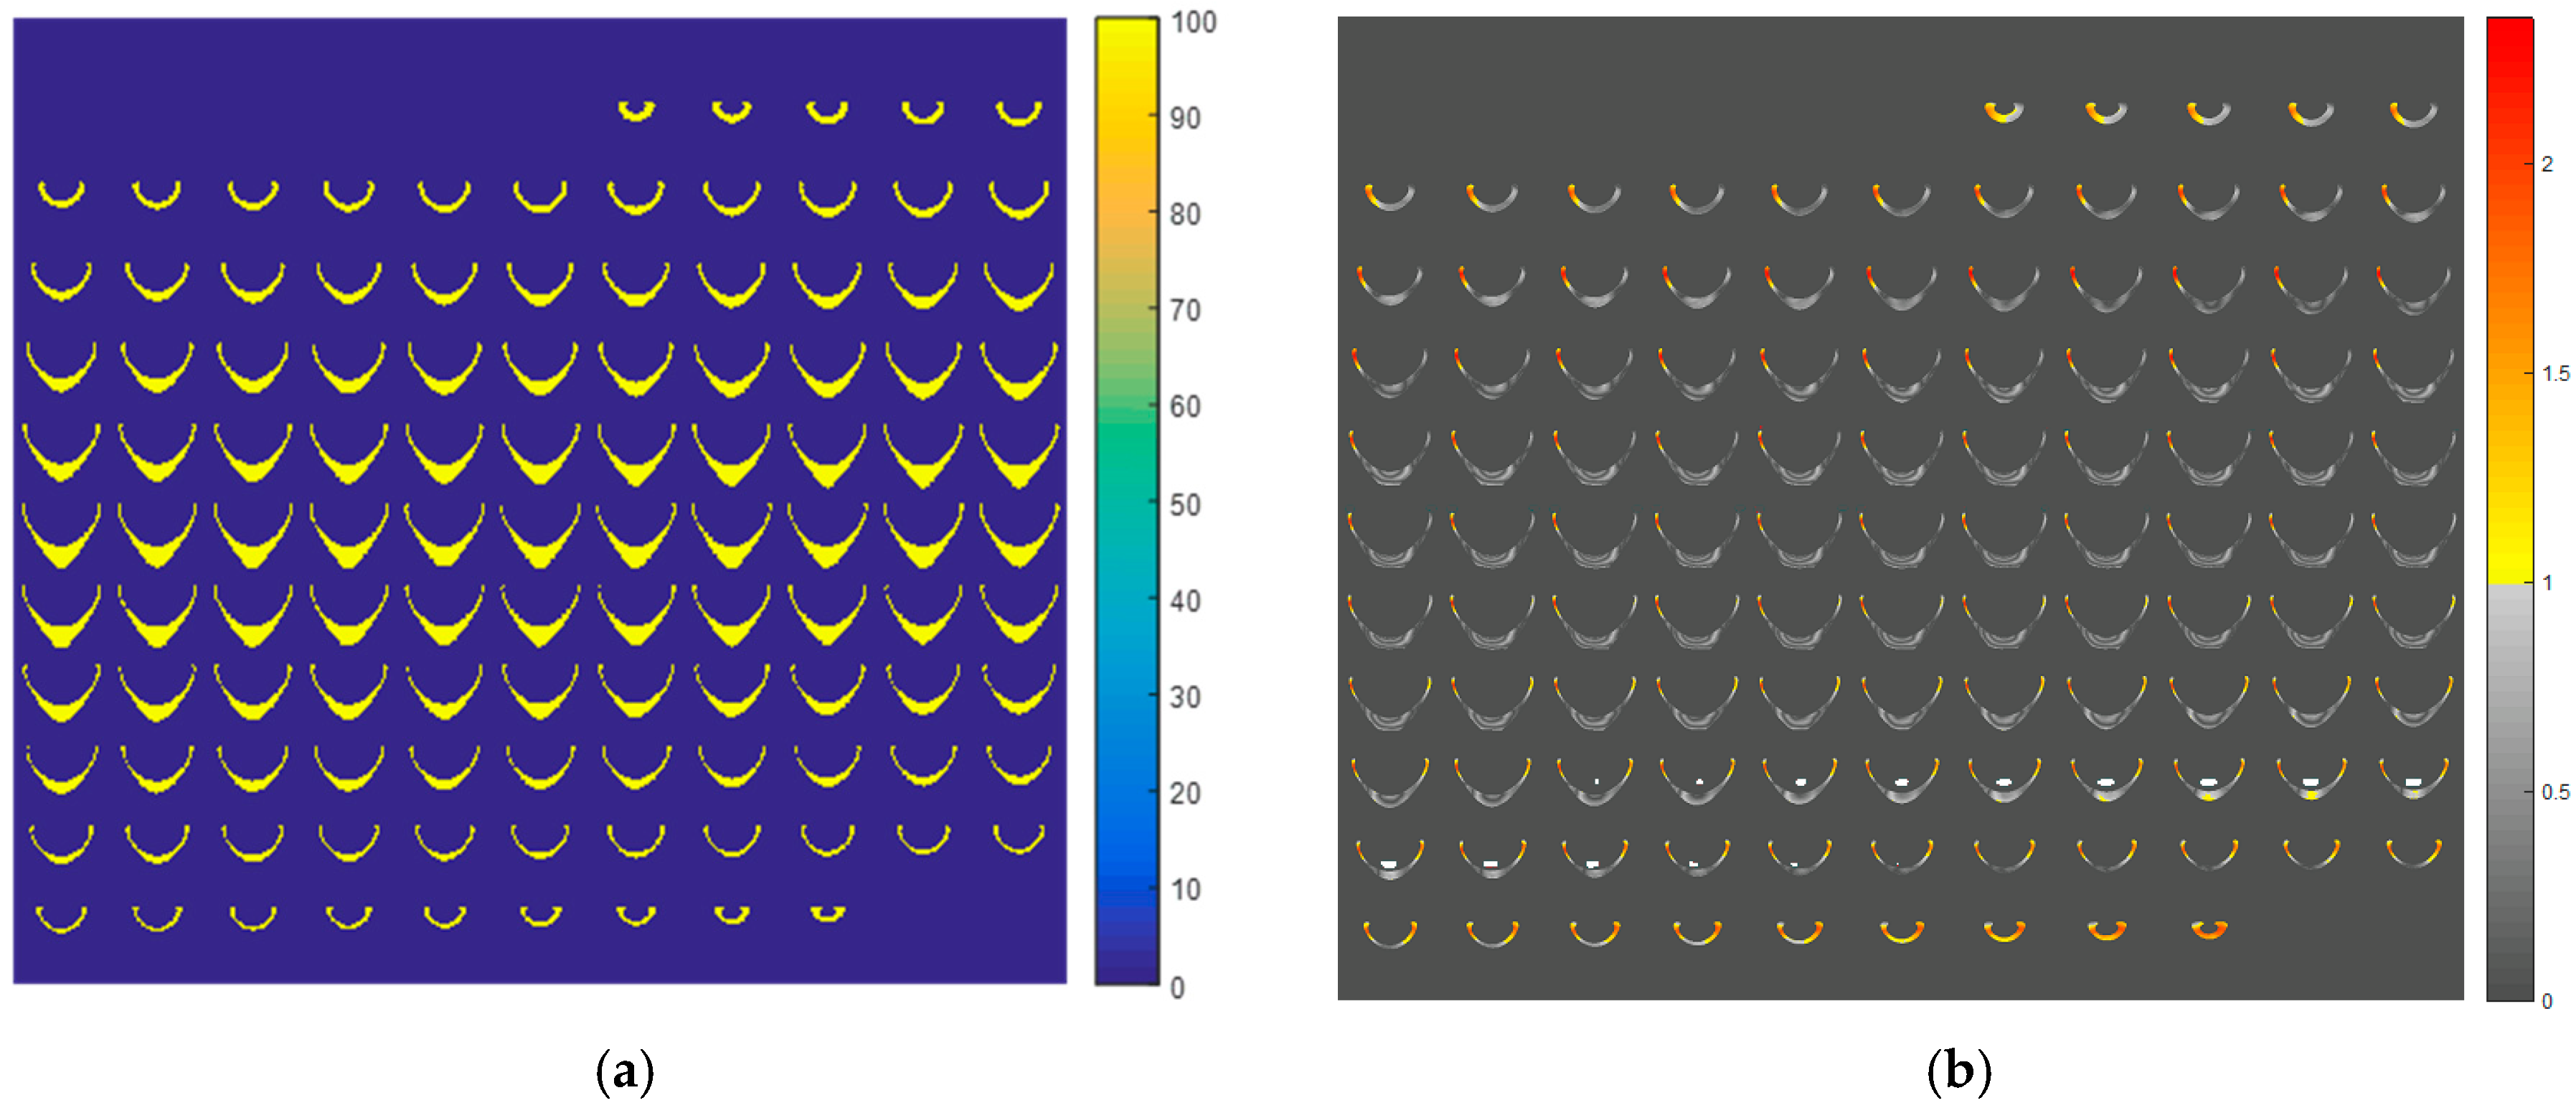

2. Results and Discussion

4. Materials and Methods